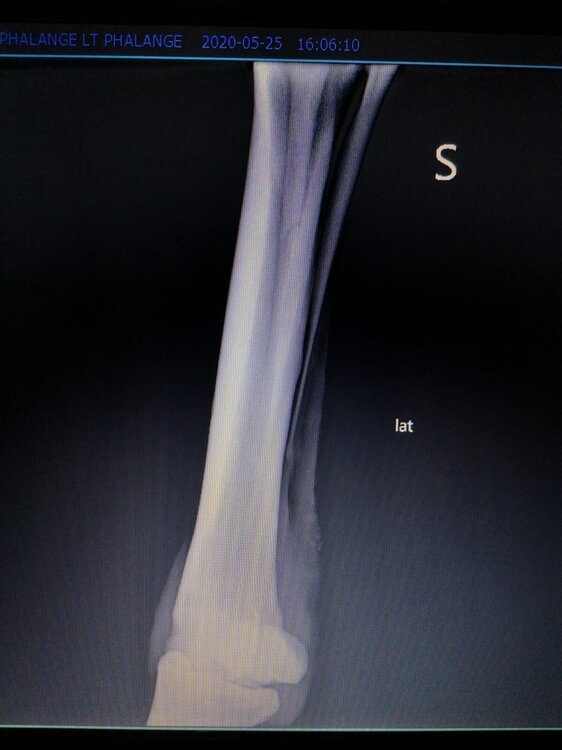

Salve volevo chiedervi qualche informazione in merce tò a un problema che ho avuto con la mia puledra. Qualche settimana fa mentre stavo lavorando alla corda è scivolata urtato l'arto posteriore sinistro. Arrivati in box ho messo dell'acqua a pressione perché si era gonfiato sia il nodello sia il pastorale. Già l'indomani l'arto era sgonfio ritornato normale, quindi ho continuato a lavorarla. Ma dopo qualche giorno di lavoro alla corda leggerissimo, al rientro in box ho notato che sia il nodello che il posturale gonfiavano nuovamente. Allora ho chiamato il veterinario che ha detto che la cavalla aveva una lussazione e mi ha insegnato come cura una fasciatura con della creta per 24h per cinque giorni e un antinfiammatorio. Dopo un paio di giorni la fasciatura ha fatto come delle vesciche e il gonfiore è aumentato dal pastorale alla garra. Abbiamo chiamato un altro veterinario abbiamo fatto vedere anche a lui la cavalla e diceva che poteva essere la frattura del ditino, ma si dovevano fare le lastre per essere sicuri. Ora abbiamo fatto le lastre e il radiologo dice che c'è dell'infiammazione ma non c'è niente di grave. Il veterinario,viste le lastre dice che deve essere operata. Allora abbiamo consultato un'altro veterinario che dice che la cavalla non ha assolutamente niente. Ora io vi allego le radiografie, datemi un vostro parere perché non só più cosa fare. Grazie